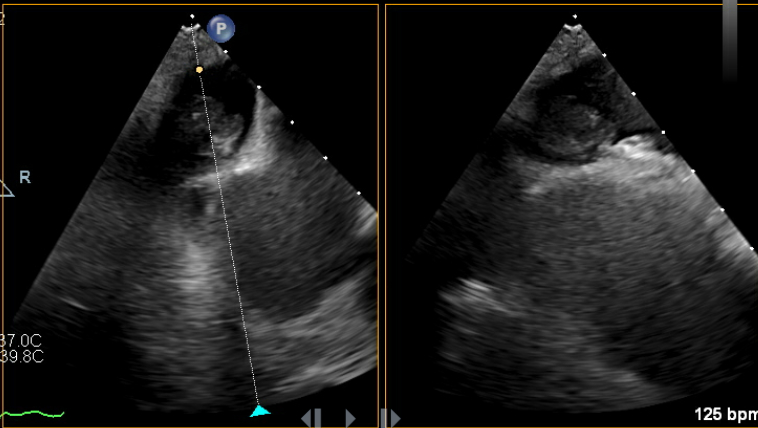

82-year-old male who presented with symptoms of progressively worsening shortness of breath and palpitations for 4 days. He was recently diagnosed with non-small cell carcinoma and underwent a left upper lobectomy a few months prior. Upon arrival, patient was tachycardic, with a heart rate in the 140s, requiring 5-6 L nasal cannula to maintain oxygen saturation above 92%. EKG revealed new onset atrial fibrillation with rapid ventricular response. Laboratory testing was remarkable for elevated NT-pro BNP to 4,000. CXR revealed bilateral pulmonary congestion consistent with pulmonary edema. Transthoracic echocardiogram was significant for severely reduced EF to 15-20%, previously normal. The patient was admitted for management of new onset-atrial fibrillation & HFrEF likely due to tachycardia-mediated cardiomyopathy. Cardioversion was initially planned; however transesophageal echocardiogram revealed an unexpected thrombus at the os of the left superior pulmonary vein. No thrombus was seen in the left atrial appendage. The patient was started on IV digoxin and low-dose esmolol drip for rate control along with a heparin drip for anticoagulation. However, the patient had sinus pauses for up to 5 seconds on esmolol drip. Given the limitation to control the heart rate, the patient underwent placement of CRT-P device. He was medically optimized and discharged with plan for outpatient cardioversion vs Atrial fibrillation ablation.

Atrial fibrillation with rapid ventricular response is a common precipitant of heart failure, often requiring rhythm control. The presence of intracardiac thrombus is a well-established contraindication due to the risk of systemic embolization. While most thrombi form in the left atrial appendage, our patient was found to have a thrombus in the left superior pulmonary vein, a unique and exceedingly rare finding. Most cases of pulmonary vein thrombosis are seen after catheter ablation, lobectomy, Lung transplantation, etc. Our case presented a unique dilemma due to the lack of guidelines addressing thromboembolic risk and cardioversion in this context. Therefore, a conservative approach was chosen with rate control and systemic anticoagulation. This case also highlights the value of comprehensive imaging like transesophageal echocardiography for through evaluation of pulmonary vein ostia in addition to left atrial appendage thrombus, especially in the context of recent thoracic surgery.